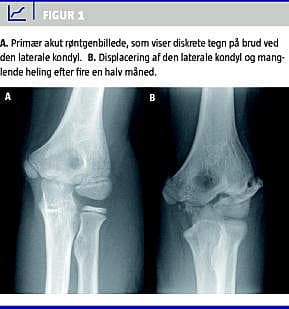

En dreng på 11 år faldt og tog fra med venstre arm. Ved den objektive undersøgelse på skadestuen fandt man hævelse samt direkte og indirekte ømhed ved radialsiden af albuen. Der blev taget røntgenbilleder af albuen i to planer, men den undersøgende læge fandt intet brud. Ved den rutinemæssige gennemgang af alle røntgenbilleder ved næste dags konference blev der erkendt brud ved den laterale humeruskondyl (Figur 1 ). Drengen blev genindkaldt, og der blev anlagt en vinkelgips og aftalt, at den kunne fjernes to uger senere hos egen læge. Der blev ikke planlagt røntgenkontrol.

Fire en halv måned senere blev han genhenvist af egen læge pga. en strækdefekt på 10-15 grader i albuen. Han havde ingen smerter. En røntgenundersøgelse gav mistanke om manglende heling ved den laterale kondyl, hvilket blev bekræftet ved en supplerende computertomografi. Efterfølgende blev der udført operation, hvor kondylen blev fikseret med en enkelt spongiosaskrue. Efter tre måneder var bruddet solidt helet, der var normal bevægelighed i albuen og ingen smerter.